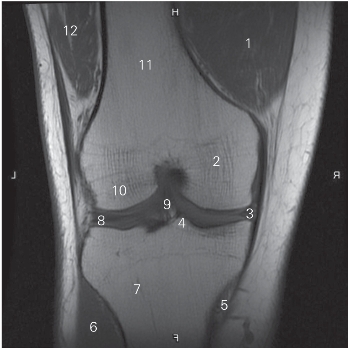

图5-28 经膝关节前份的冠状断层MR T1加权图像

1 股内侧肌 vastus medialis 2 股骨内侧髁 medial condyle of femur

3 内侧半月板 medial meniscus

4 胫骨髁间隆起 intercondylar eminence of tibia

5 半膜肌腱 tendon of semimembranosus

6 胫骨前肌 tibialis anterior 7 胫骨 tibia

8 外侧半月板 lateral meniscus

9 前交叉韧带 anterior cruciate ligament

10 股骨外侧髁 lateral condyle of femur

11 股骨体 shaft of femur 12 股外侧肌 vastus lateralis